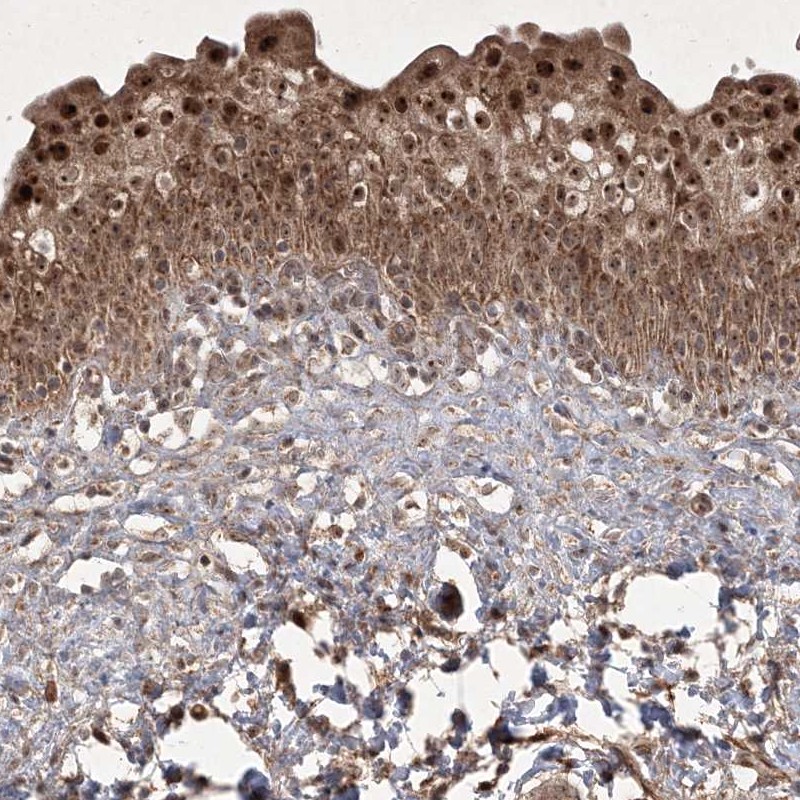

Immunohistochemical staining of human urinary bladder shows strong cytoplasmic and nuclear positivity in urothelial cells.